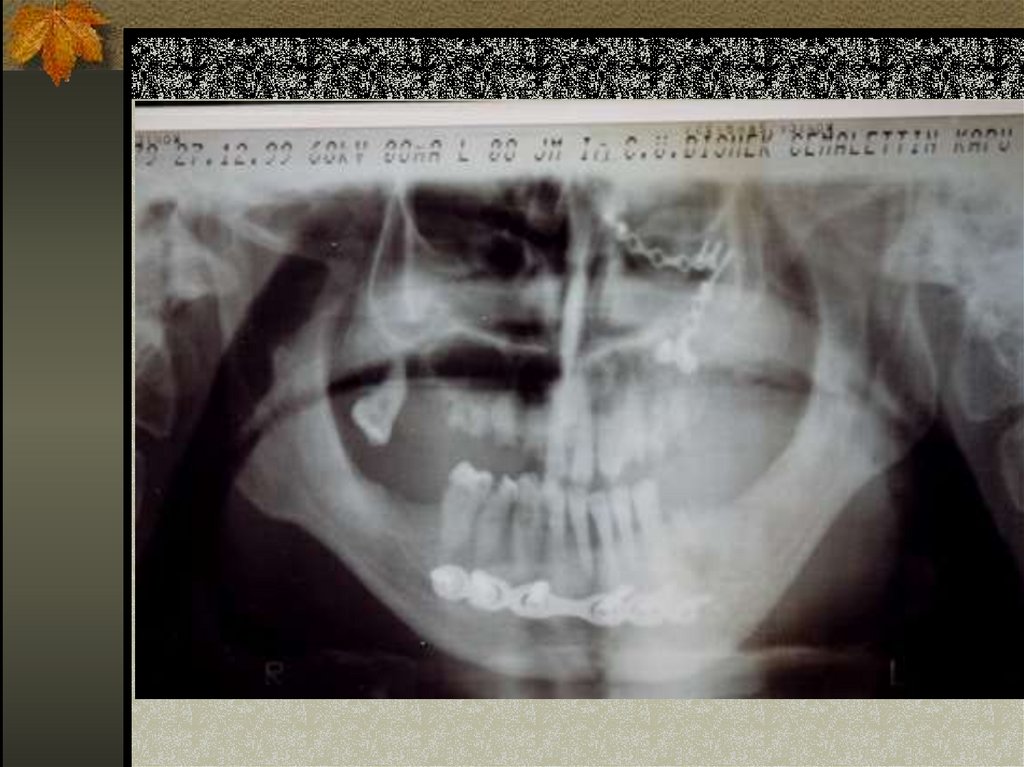

13. DİŞ TESBİT APAREYİ-ŞİNE

14. BÜKÜM ŞİNE

15. İKİ PARÇA DÖKÜM ŞİNE

16. AÇIK GUTİER (Splint)

17.

18. AÇIK GUTİER

19. GUNNING SPLİNT